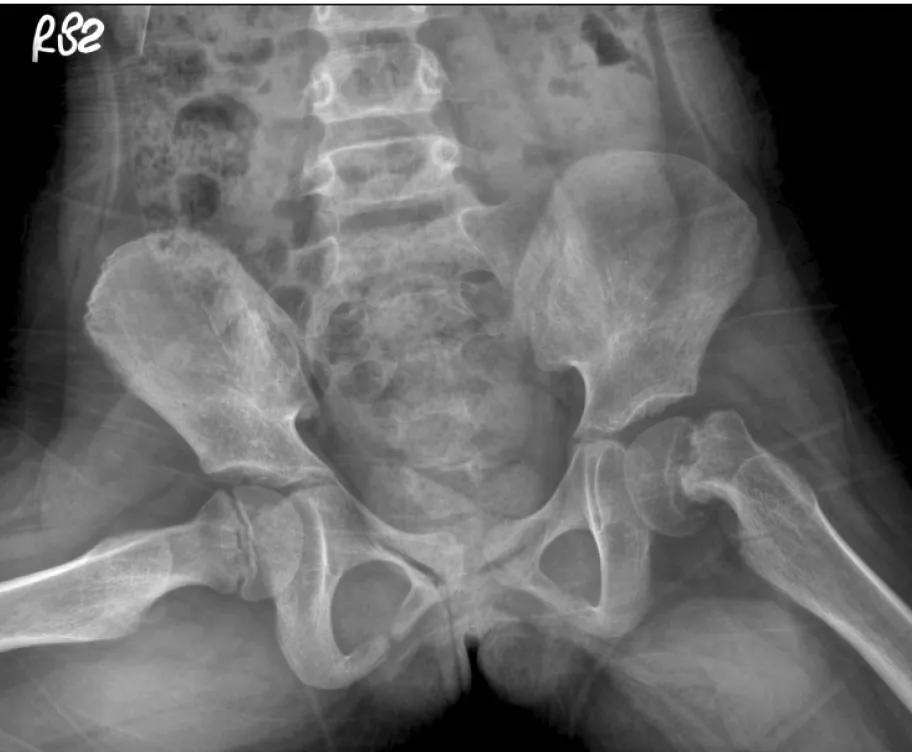

【106-2 醫學(五) 第74題】15歲男生因鼠蹊部疼痛跛行而求診,其青蛙姿勢X光如圖示,則最可能診斷為何?